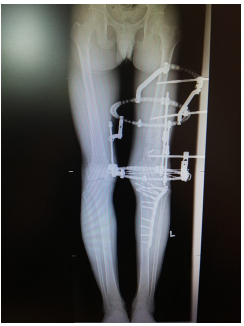

He underwent removal of implant, corrective osteotomy, left Illizarov external fixation and gradual deformity correction (Figure 3). Intra- operatively there was no local signs of infection to the distal femur and intra- operative cultures came back nil of growth/ organism. At ten weeks post-operative the deformity was corrected (Figure 4).